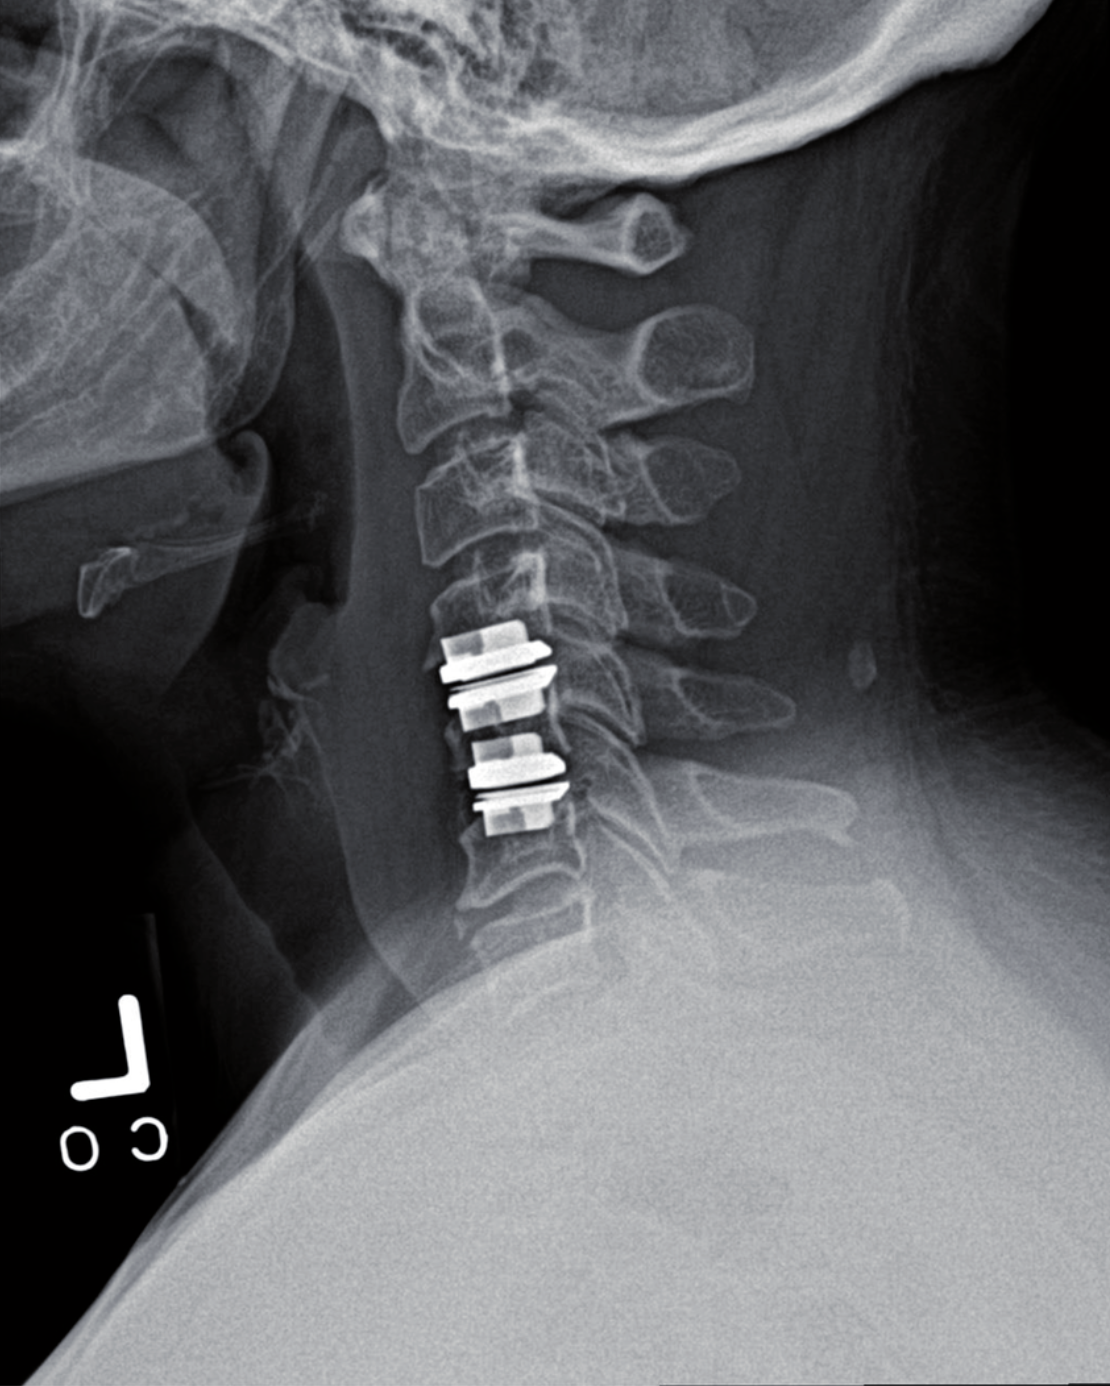

SPINE

• Procedures include discectomy, laminectomy, spinal fusion, and cervical arthroplasty

• Minimally invasive procedures designed to reduce pain and speed recovery

• Focused on restoring mobility and returning patients to the activities they love

Our spinal procedures help patients regain comfort, mobility, and confidence with approaches tailored to their needs.